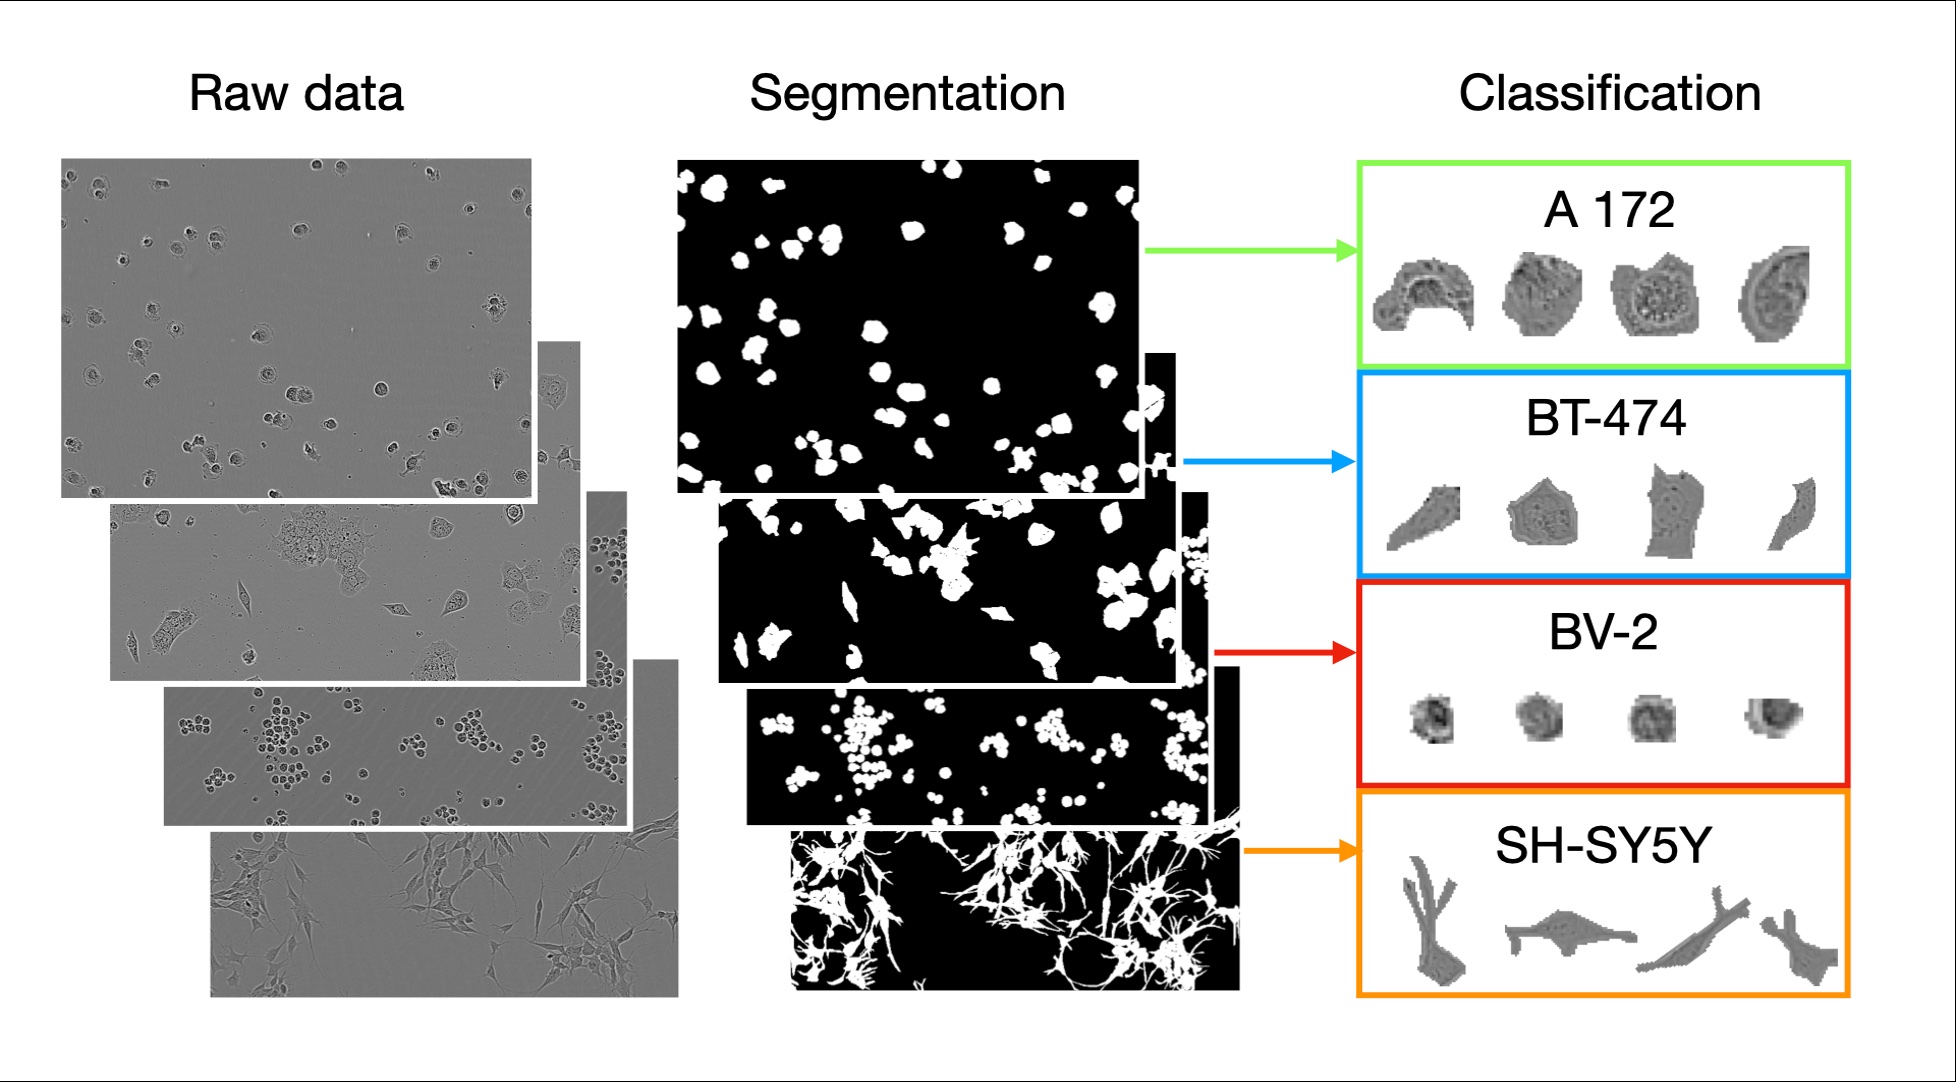

LIVECell pipeline: phase-contrast images → instance segmentation → single-cell classification

LIVECell pipeline: phase-contrast images → instance segmentation → single-cell classification